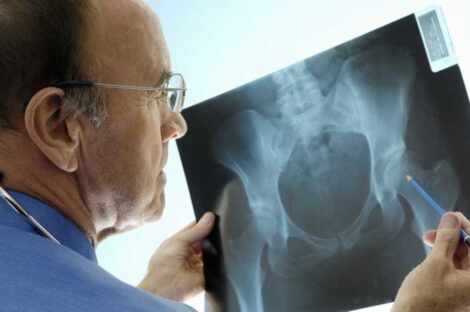

اكتشفت مجموعة من الدراسات أن منع مستقبلات معينة في الدماغ يؤدي إلى نمو عظام قوية بشكل ملفت، حيث قام العلماء…